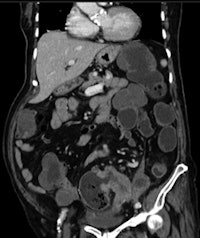

Acute ileal involvement by Crohn's disease, with wall thickening and mucosal enhancement.

Many other gastroenterological pathologies require imaging for detection and evaluation. Ultrasonography is the first step when liver, pancreatic, or biliary disease is suspected. In inflammatory bowel diseases, CT and more recently MRI have proved to be valuable tools for detecting and staging the disease, as well as for monitoring treatment.